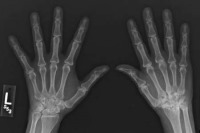

آرتریت روماتویید دومین شکل رایج آرتریت (پس از آتروز) است. این شکل از آرتریت نوعی اختلال خود ایمنی است که در آن سیستم ایمنی بدن به اشتباه به سلول های سالم حمله می کند. این اختلال اغلب از میانسالی آغاز می شود و با درد، تورم، سفتی عضلات و مفاصل و اختلال حرکتی همراه است. آرتریت روماتویید معمولا به مچ دست و انگشتان حمله می کند. التهاب ناشی از آرتریت روماتویید به راحتی می تواند به بخش های دیگر بدن از جمله چشم ها، دهان و ریه حمله کند. این بیماری از طریق دارو و جراحی قابل درمان است.

پوکی استخوان یکی از شایع ترین عوارض جانبی آرتریت روماتویید است و مطالعات جدید نشان می دهد با درمان زودهنگام این عارضه می توان تا حد زیادی از پوکی استخوان جلوگیری کرد.